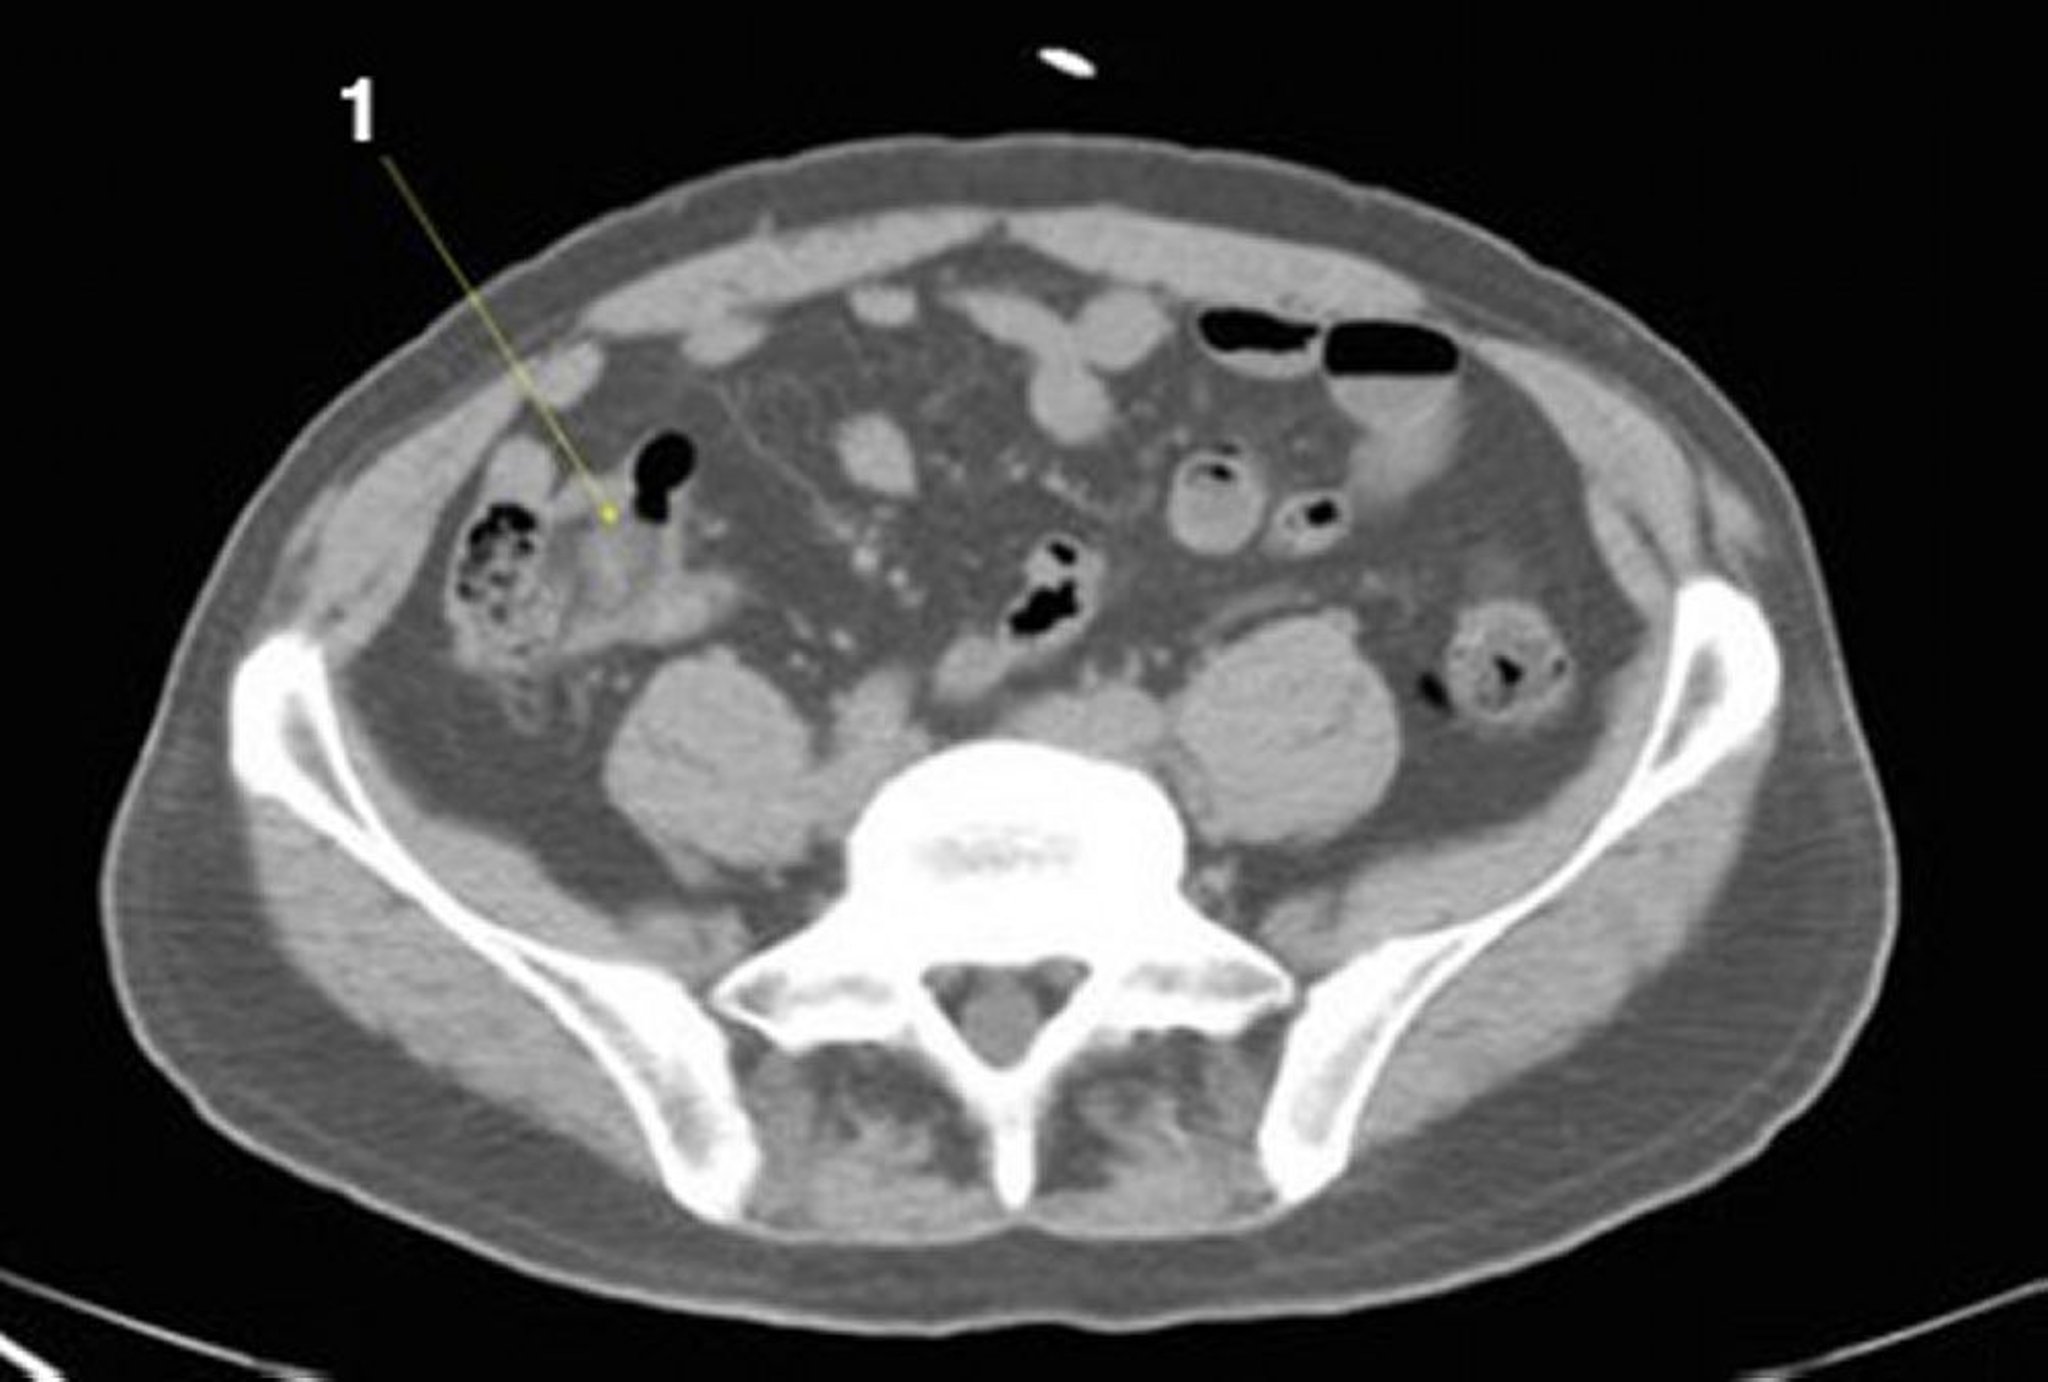

TC senza contrasto dell'addome e della pelvi che mostra un'anatomia normale (Slide 21)

1 = ileo.